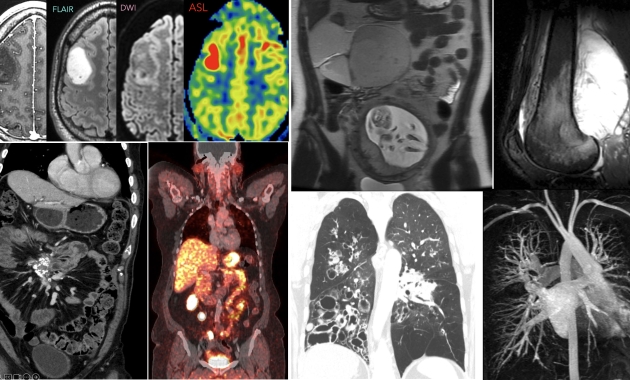

For over 50 years, UCSF Radiology has been a leader in Continuing Medical Education (CME). We are looking to continue that tradition and provide new and exciting destinations. Our 2025 course calendar is complete and available for review on Course Calendar link. In addition to our annual Big Island Hawaii courses in the first quarter, we will also be offering programs in Palm Springs, Napa, Alaska, Sorrento-Italy, and Maui, and then ending the year with a warm-up course in Puerto Rico. Most courses provide a mixture of subspecialties in a practical and clinically relevant format in addition to specific core programs in Body, Neuro/MSK, Breast, and Ob/Gyn Imaging. As we look to 2026, we plan to continue our three Big Island Hawaii courses as well as a new course in Split, Croatia in the fall with other destinations currently being reviewed. For the most up-to-date information follow our social media accounts. We hope that you’ll join us in one of these amazing destinations. Please contact us if you have any questions.